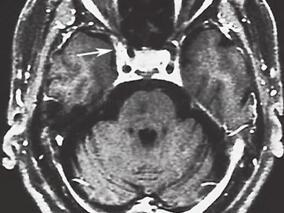

1小时条评论【病例资料】 患者,女性,32岁,医师。因左侧肢体麻木5个月,右侧肢体无力12天,于2005年6月3日收入北京医院神经外科。 现病史:患者于5个月前(2005年1月17日)无明显诱因出现左侧肢体麻木,无力弱、头痛、发热,在当地医院行头颅CT检查未见明显异常,予灯盏花素...